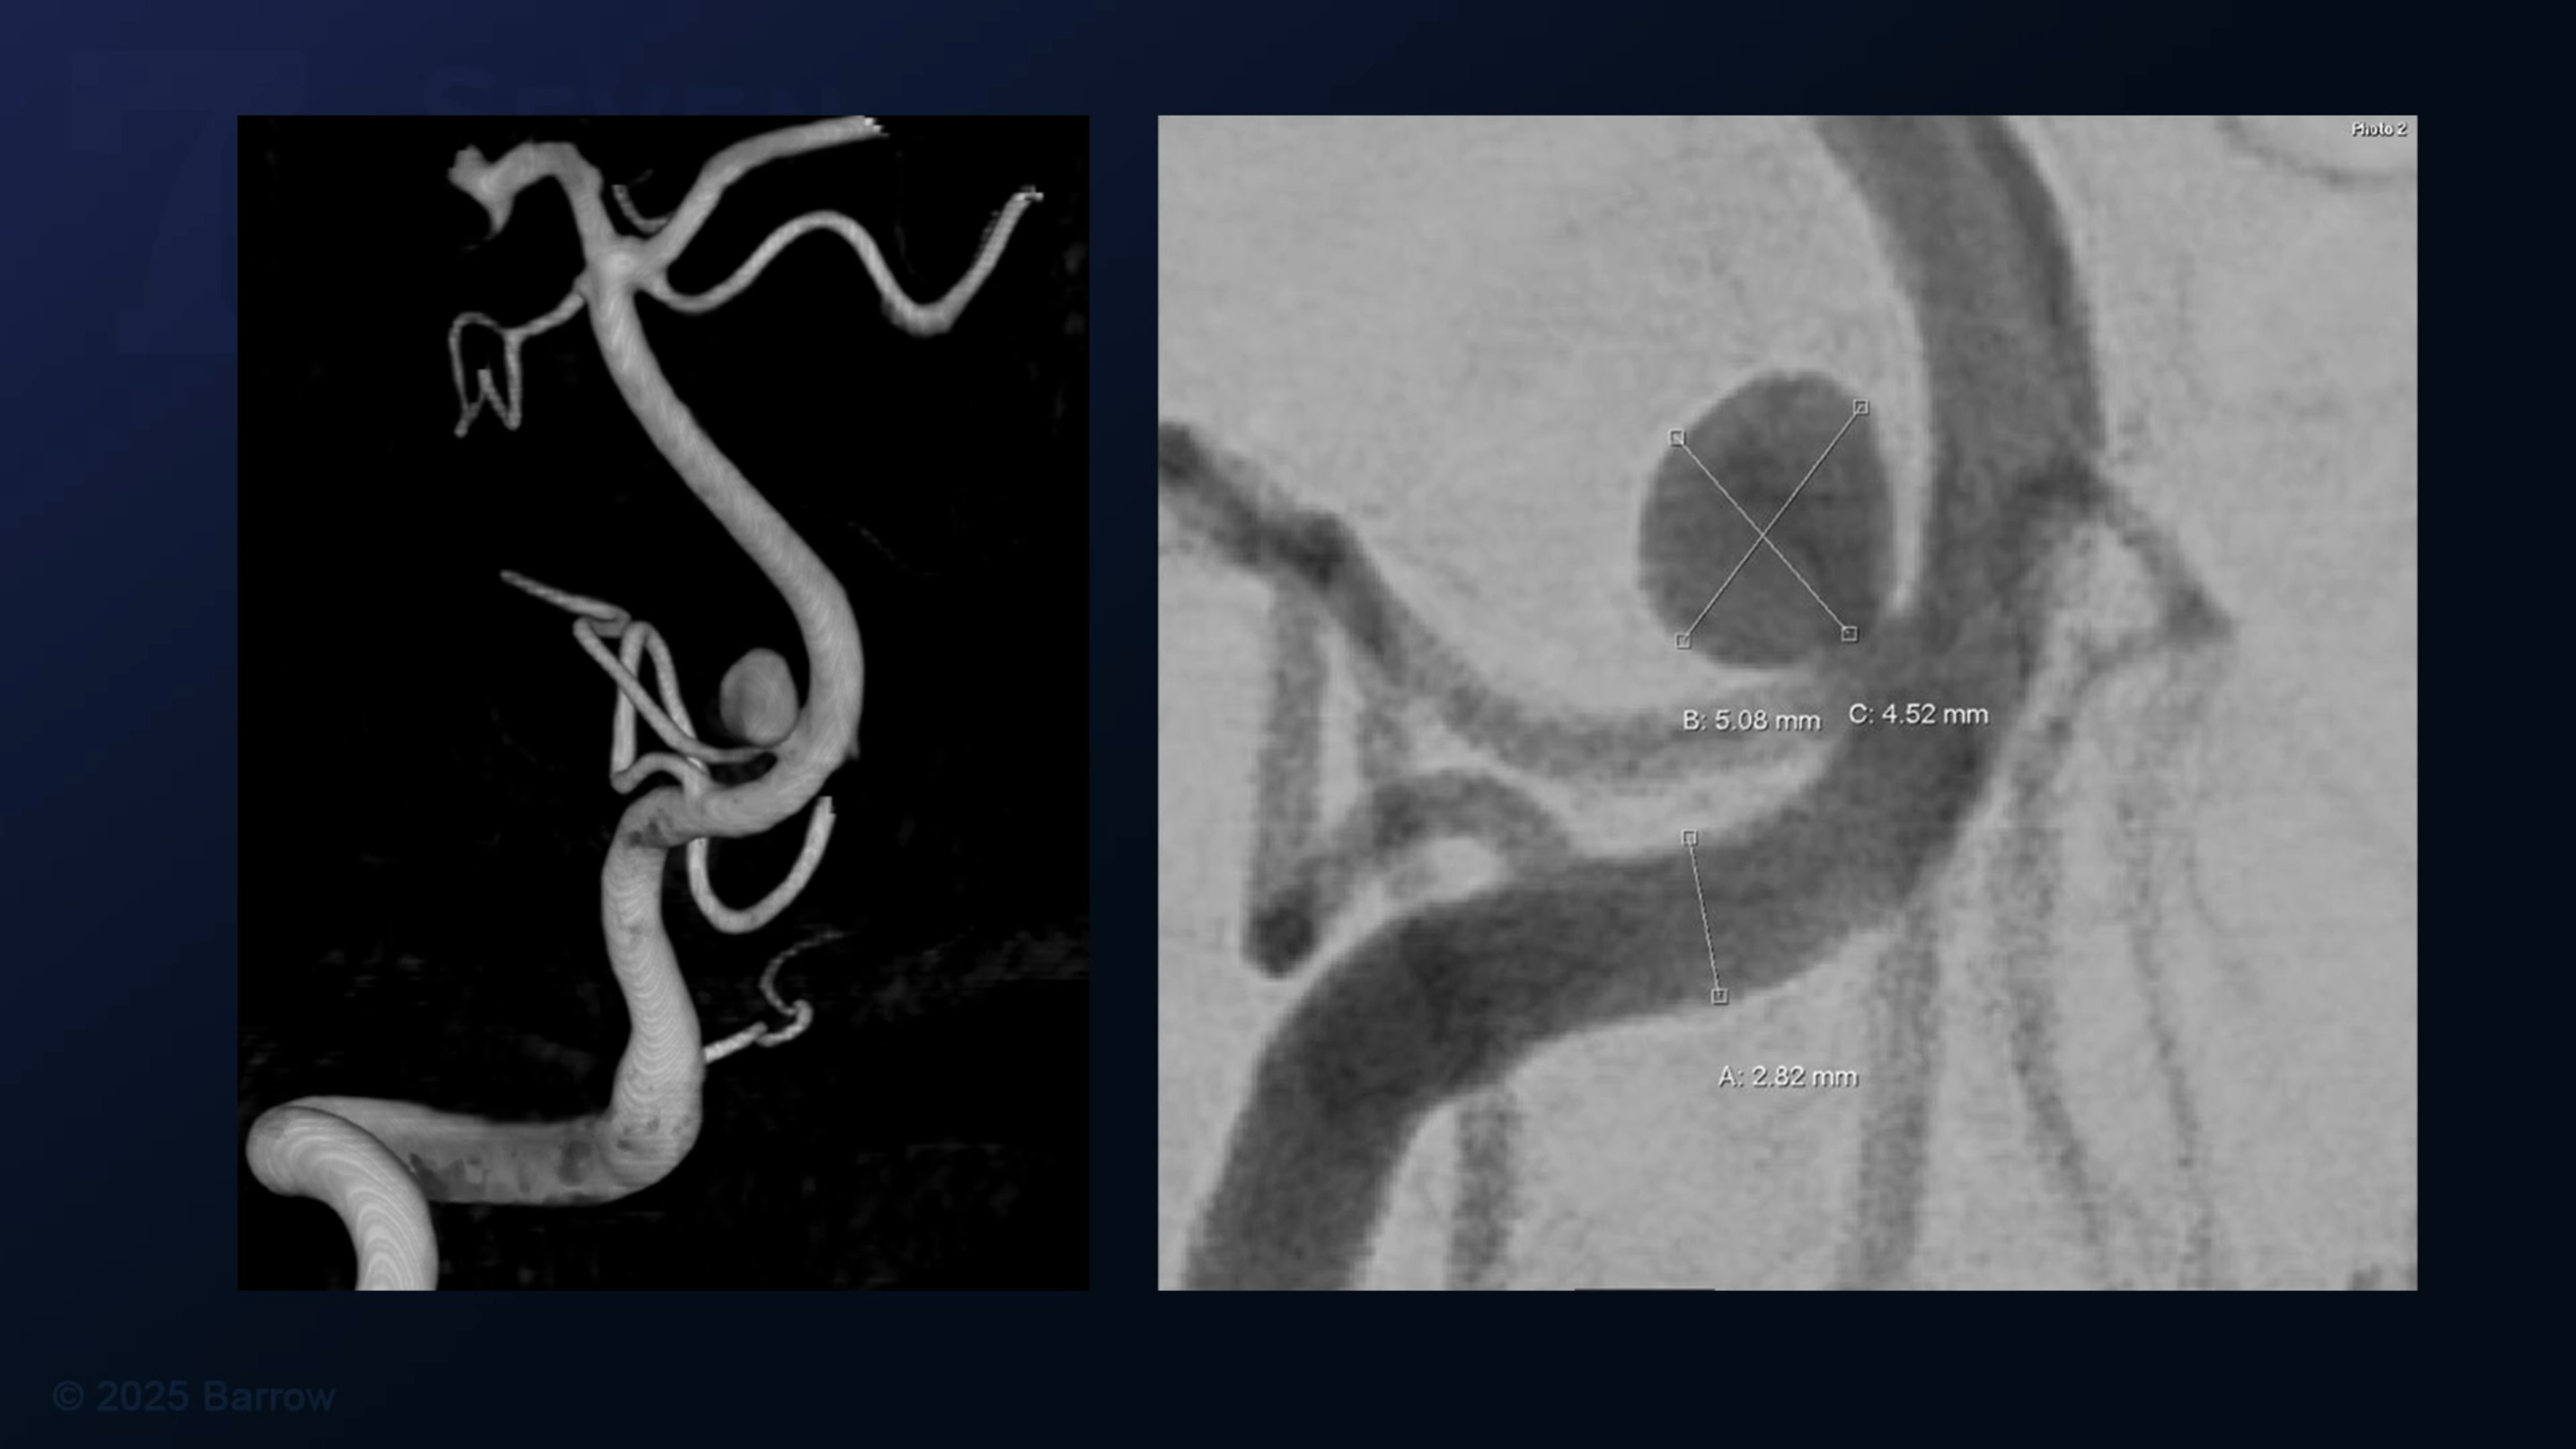

#495: Microsurgical Clipping of an Unruptured Anterior Inferior Cerebellar Artery Aneurysm

Episode 495 of Seven Series shows a microsurgical clipping of an unruptured anterior inferior cerebellar artery (AICA) aneurysm,